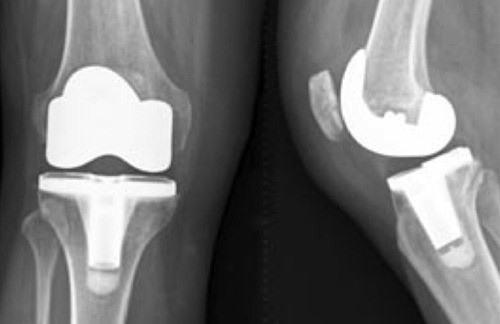

| [건강설계]매우 까다로운 인공관절 재치환술 | |||||

[건강설계]매우 까다로운 인공관절 재치환술 |